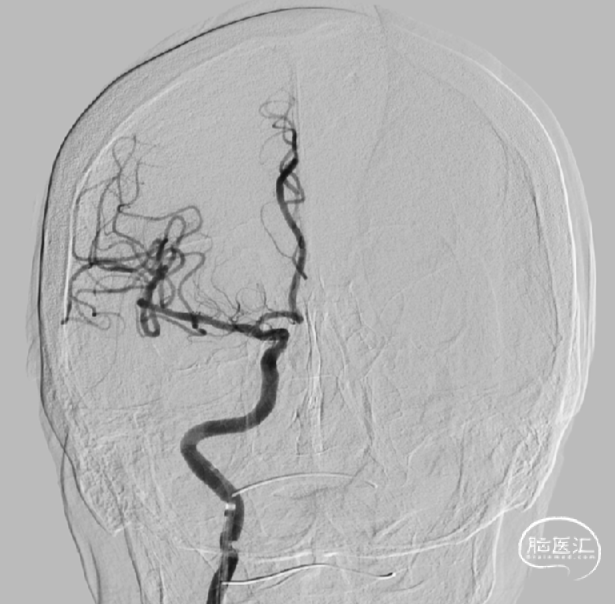

脑血管造影示右侧大脑中动脉M1分叉处致M2上干栓塞,远端血流缓慢。

在Tethys®中间导引导管内造影示右侧大脑中动脉M1段通畅,mTICI分级3级。